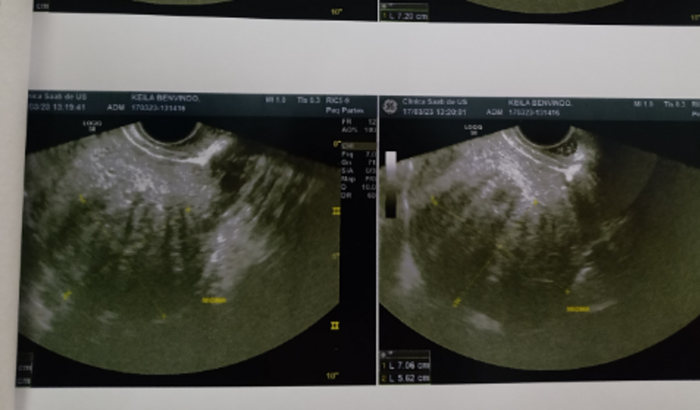

Olá pra quem não me conhece sou a Keila criei essa vaquinha para estar conseguindo o valor de 11 mil para pagar minha cirurgia descobri no ano passado um mioma (tumor )no meu útero e um cisto no ovário esquerdo tentei um tratamento que o médico passou para ver se conseguia diminuir ou parar o crescimento do Mioma no útero ( tumor) mais infelizmente sem sucesso durante o tratamento o tumor cresceu mais em 6 meses ele passou de 4 cm para 7 cm meu útero está muito maior que o Tamanho normal de um útero e o ovário esquerdo tbem está devido ao cisto no tamanho de 4 cm que desenvolveu tbem no meu ovário e agora para eu ficar bem denovo e não sentir mais dores que vem sendo frequente e cada vez mais forte me impedindo de ter minha rotina normal o médico disse que só eu operando qualquer ajuda e bem-vinda seja doando ou compartilhando em redes sociais whatsapp para